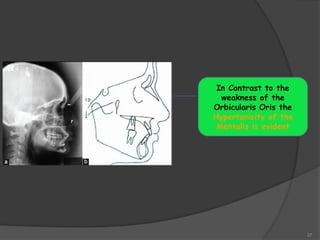

In Contrast to the

weakness of the

Orbicularis Oris the

Hypertonicity of the

Mentalis is evident